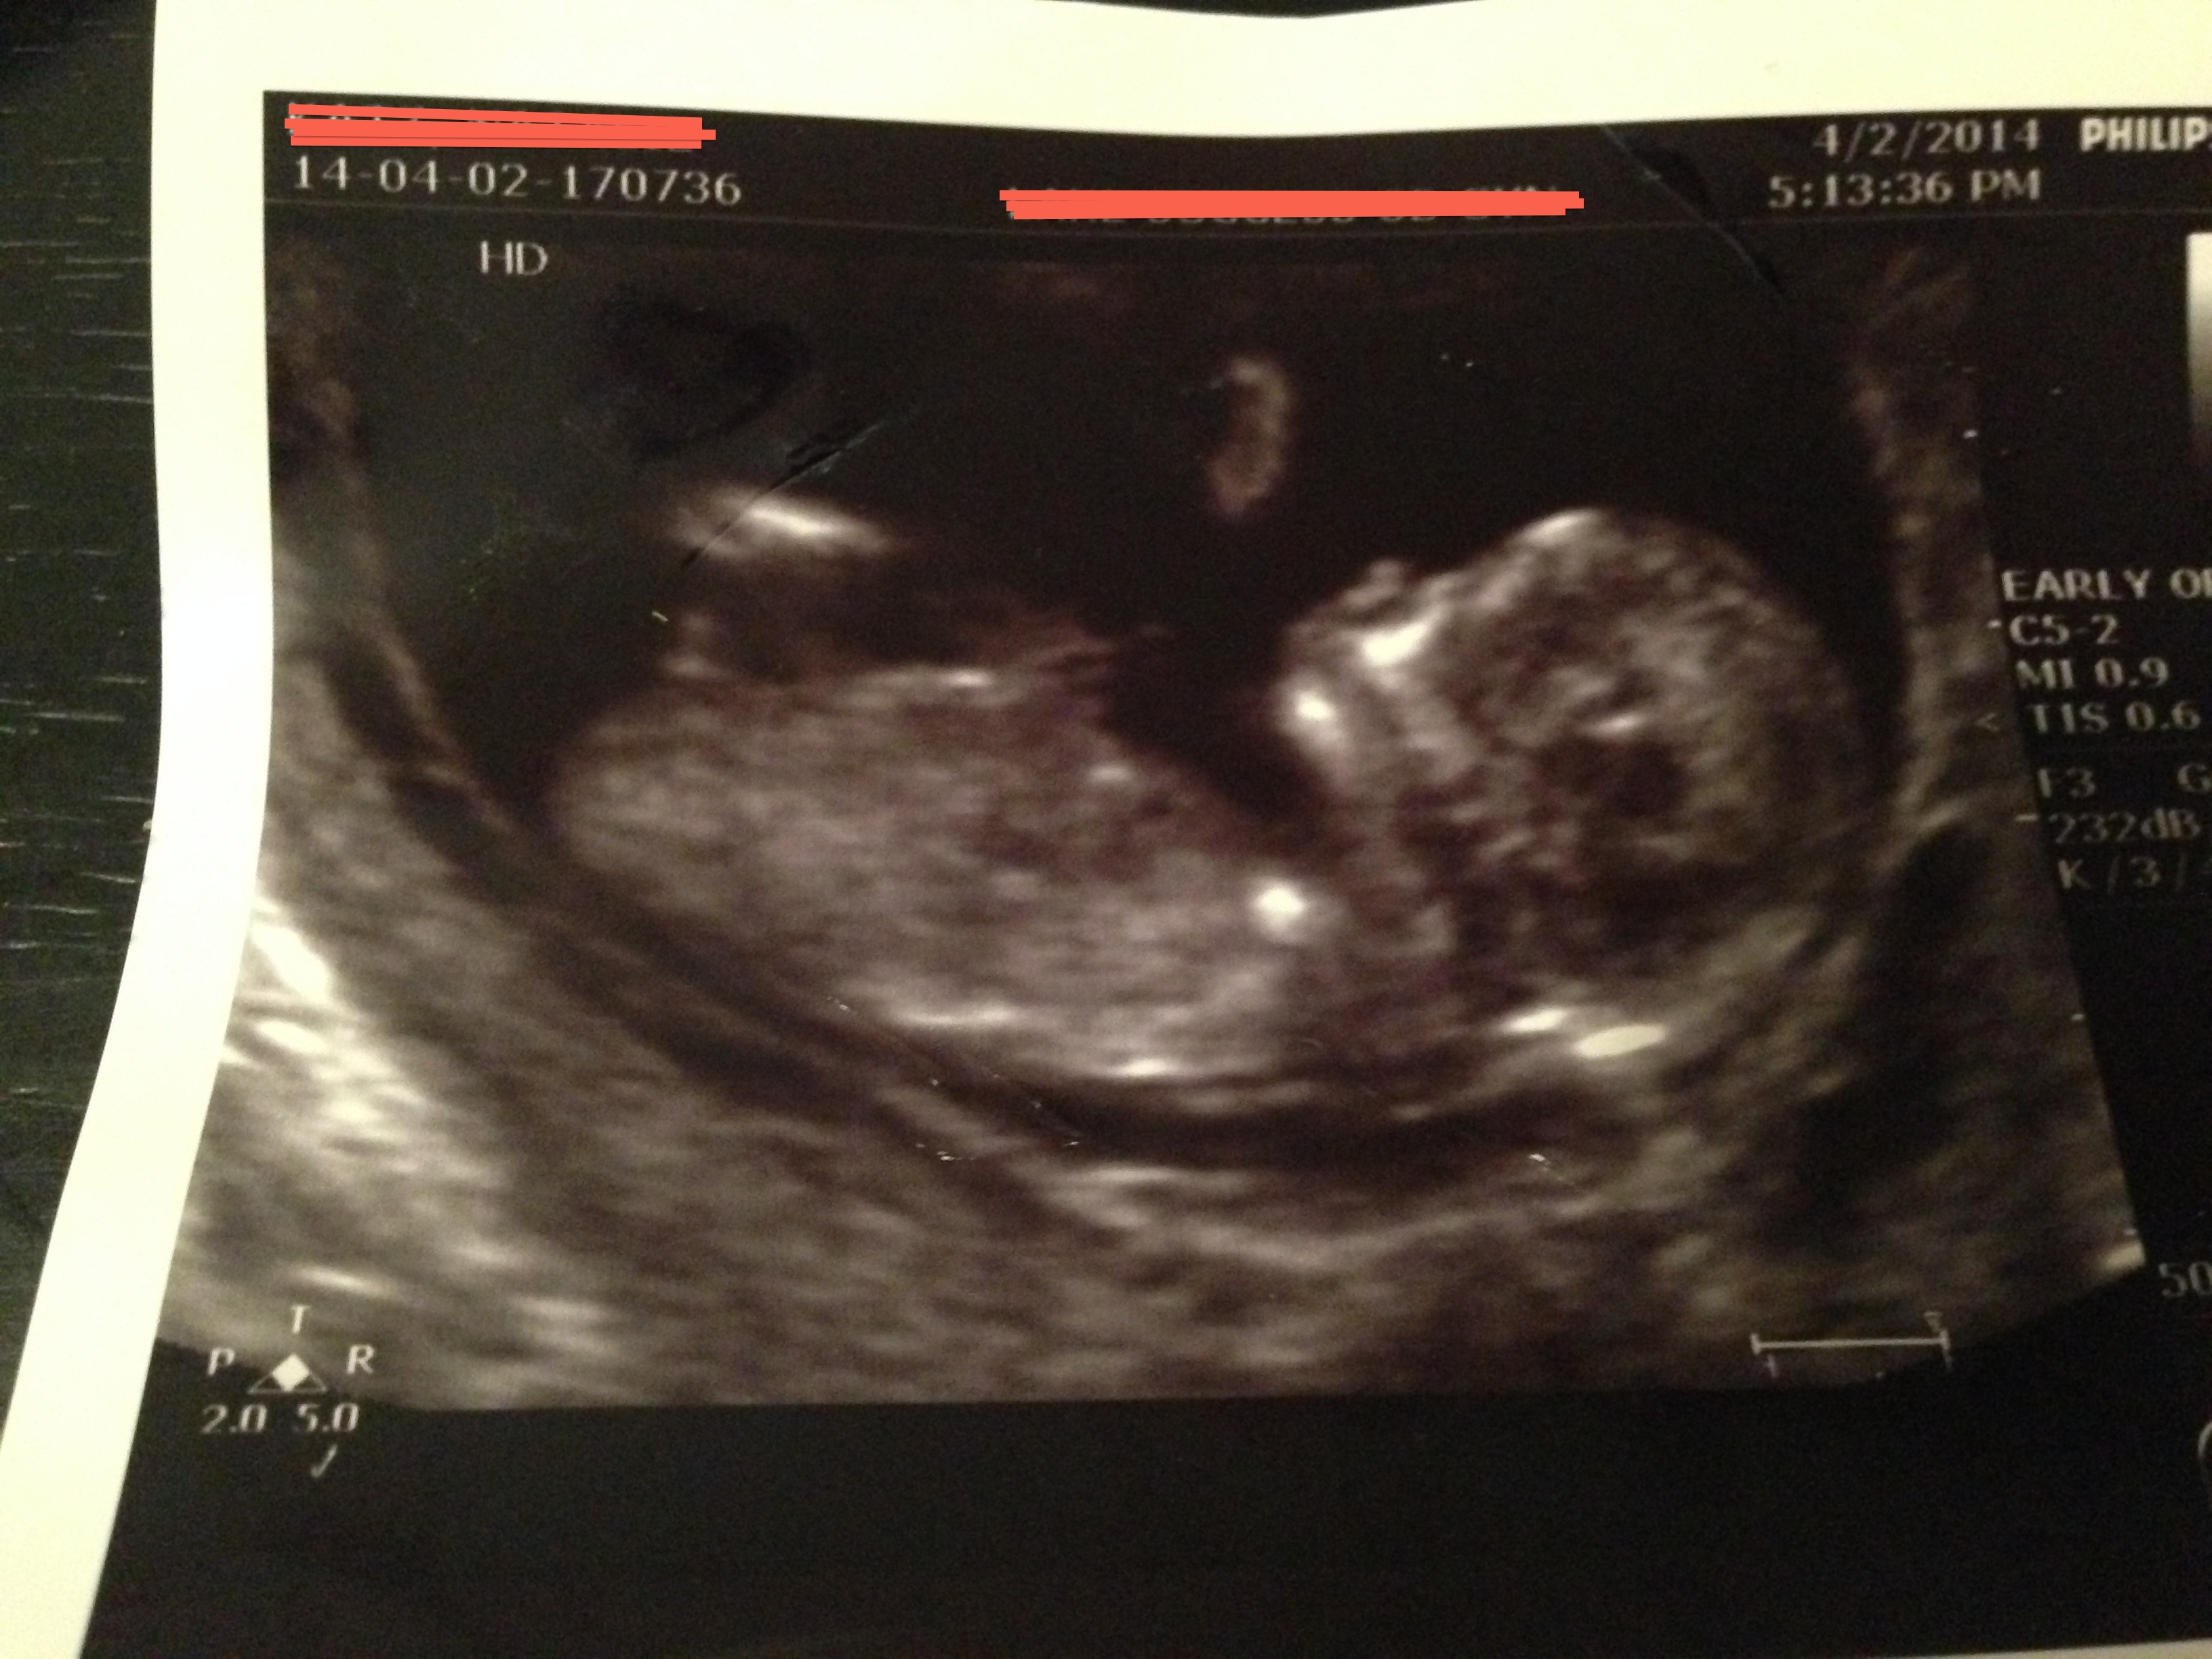

This is for a friend. At first I thought girl, but then I thought I saw stacking. What do you think? She is 12 weeks exactly.

The new pic appears to have a very boy nub if that in fact is the nub:)

Very boy

The new pics look boyish to me, but what I see might be part of a leg or cord, so just a tentative guess xx